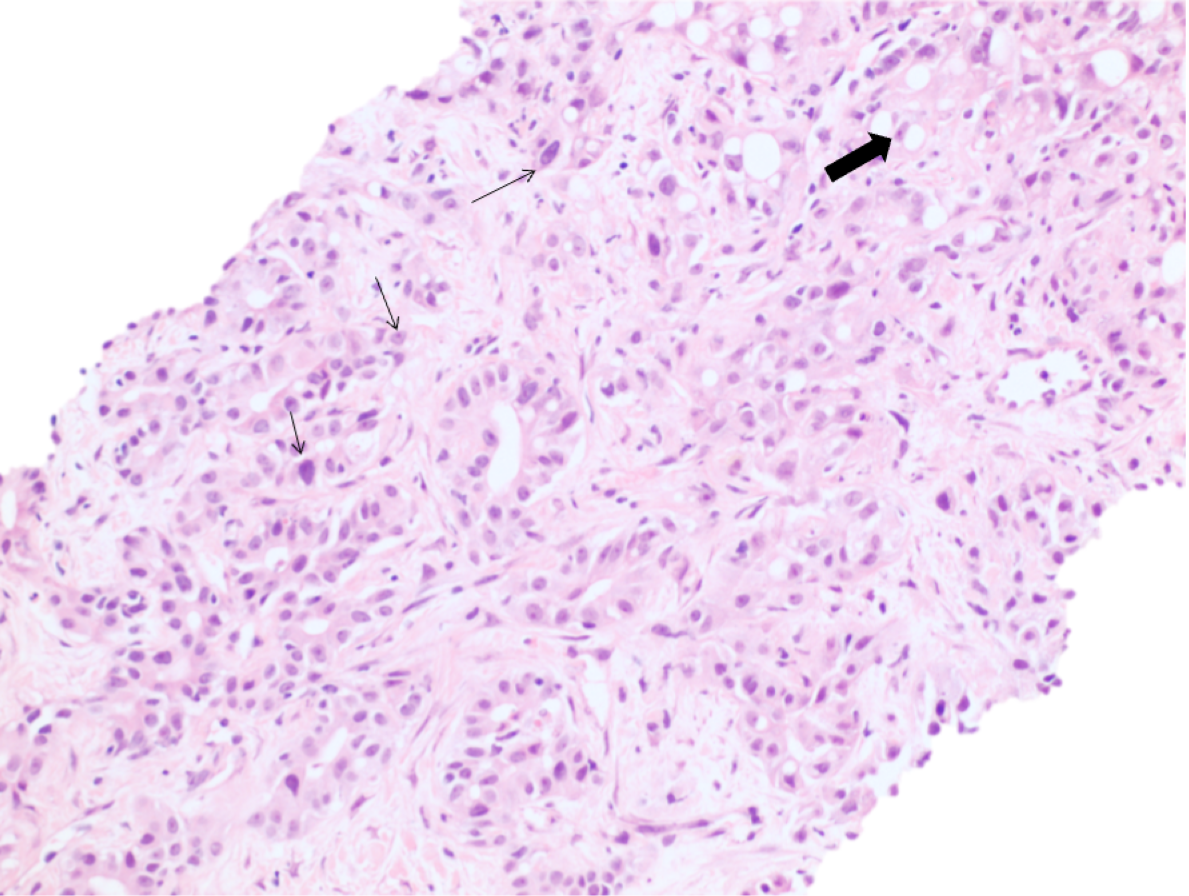

At low power, the liver core shows irregular angulated glands and single cells in a background of abundant desmoplastic stroma. (Figure 1 and 2). At high power the cells display varying degrees of cytologic atypia (Figure 3), consistent with a moderate to poorly differentiated adenocarcinoma. Immunohistochemical stains for CK7 (Figure 4) and CK19 (Figure 5) are positive. Immunohistochemical stains for Glypican-3, Arginase-1, CK20, GATA3, PAX-8 and CDX-2 are negative. In the clinical context of a single central intrahepatic lesion with absence of lesions in the rest of the body, the histologic findings are compatible with intrahepatic cholangiocarcinoma.

Figure 3: High magnification showing cells with varying degrees of cytologic atypia (thin arrows) and areas with signet ring cell features (thick arrow)